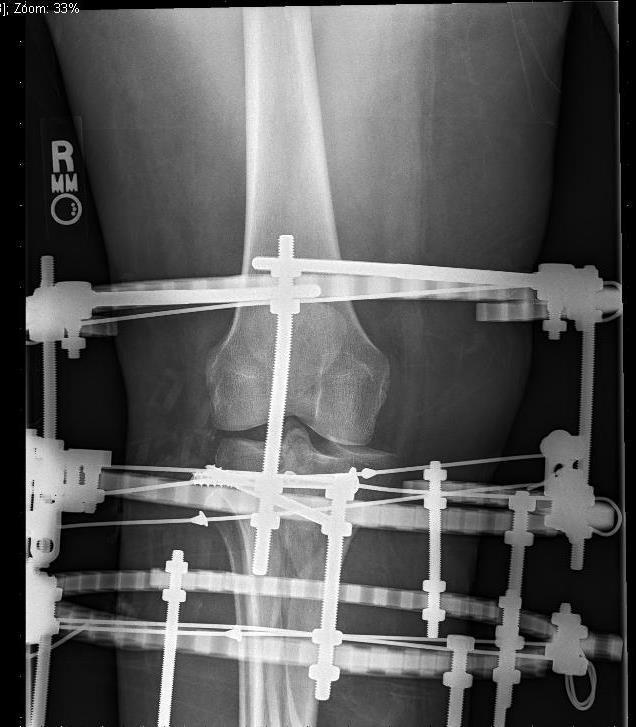

Апарати зовнішньої фіксації

Показання – відкриті переломи з дефектом шкірних покривів та мʼяких/кісткової тканини

- Технічно складний метод (потребує досвіду)

- Не забезпечує анатомічної репозиції та міжуламкової компресії (остеопороз)

Переваги:

- Малотравматичність

Недоліки:

- Ризик інфекції

- Побутові незручності для пацієнта

- Точне відновлення суглобових поверхонь

Може використовуватися як етапне лікування з наступною заміною метода фіксацію

Зовнішня фіксація використовується як тимчасовий захід при відкритих переломах, політравмі, тяжкому ушкодженні м'яких тканин або як остаточний метод у складних випадках.